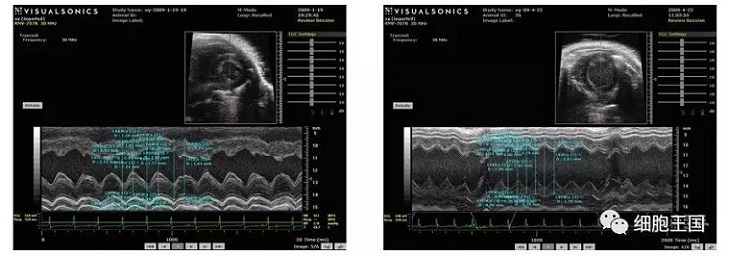

干細(xì)胞移植后各臟器呈現(xiàn)較之前狀態(tài),具體表現(xiàn)在以下幾個方面(如圖)。

超聲心動圖顯示對照組左室舒張期容積低于移植組